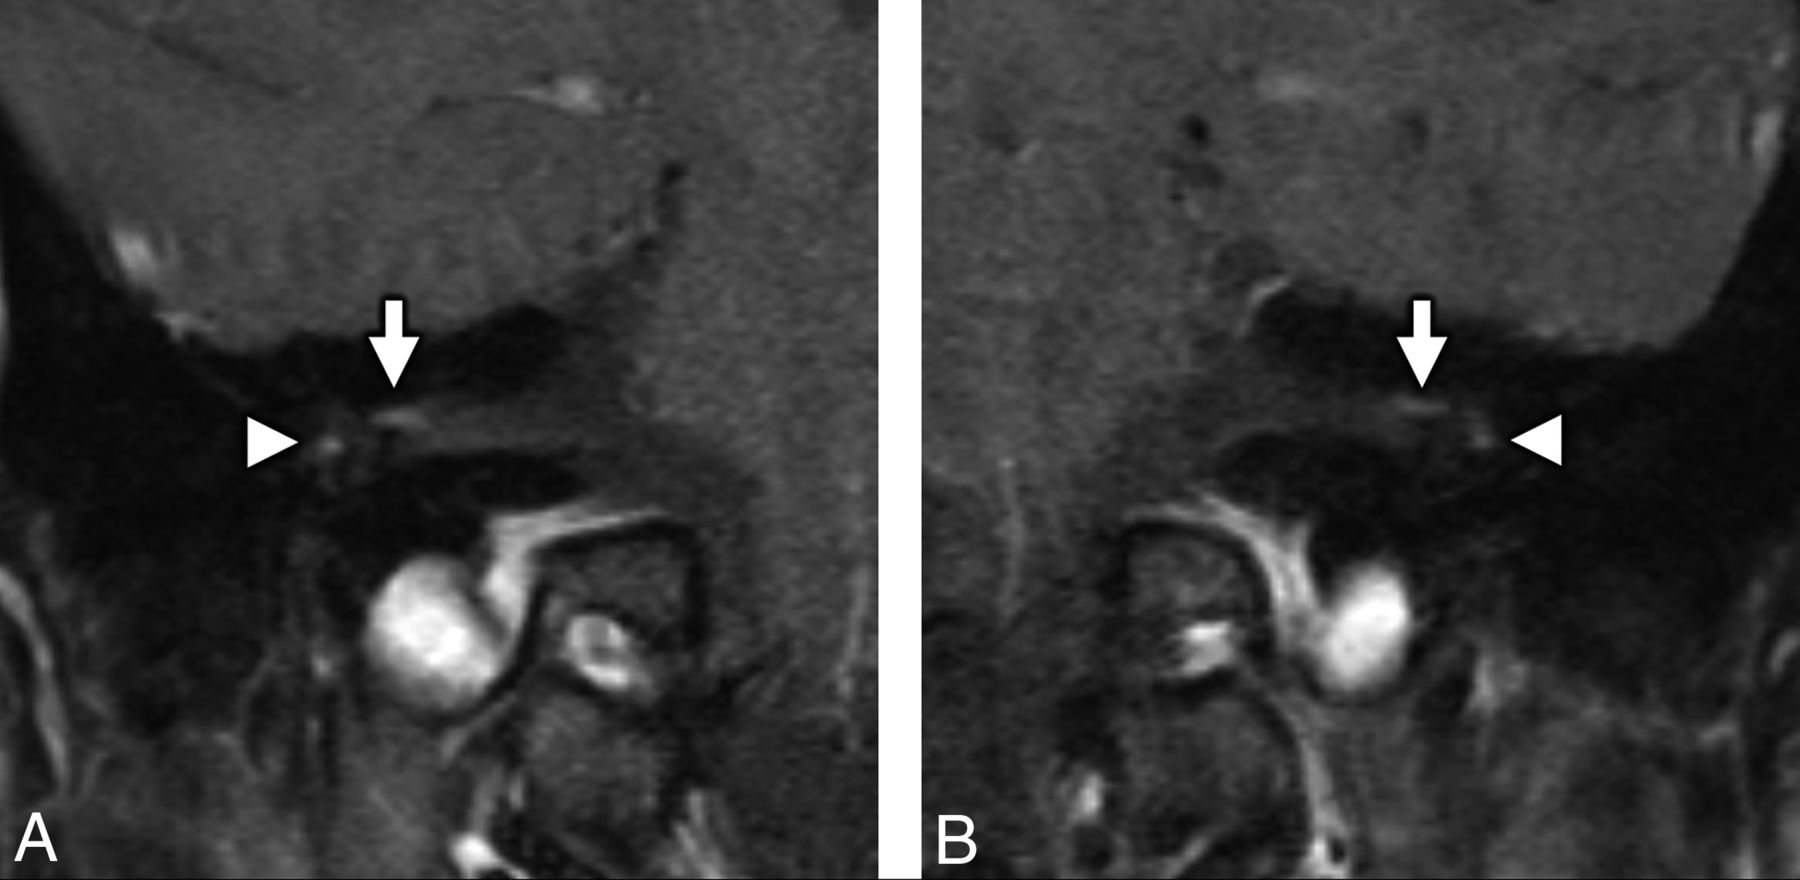

MR imaging of the temporal bones in a patient with antecedent COVID-19 and new-onset bifacial weakness and paresthesia subtype Guillain-Barré syndrome. Coronal postcontrast T1-weighted fat-saturated MR imaging of the right (A) and left (B) temporal bones demonstrates abnormal “tuft-like” enhancement at the anterior-superior fundus of the internal auditory canal bilaterally (white arrows), corresponding to the distal canalicular segments of the facial nerves (CNVII). Note additional contrast enhancement along the tympanic segments of the facial nerve bilaterally (white arrowheads), which is greater in degree than typically encountered. Enhancement along the canalicular segments of the facial nerves (white arrows) is always considered abnormal on MR imaging, though mild tympanic segment enhancement is considered within normal limits.